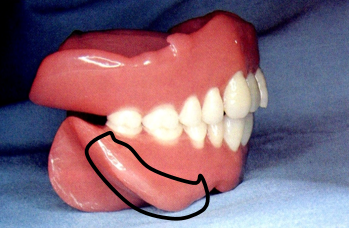

10.颤动线(vibrating line)

位于软腭与硬腭的交界部位。发“啊”音时软腭升高,发音结束后又复归原位,故又称“啊”线。

堵住鼻孔用鼻子出气会使软腭向下降,能明确观察到颤动线。

该线通常作为决定义齿基托后缘的标志,分前、后颤动线,两者之间为后堤区,宽约2~12mm 。